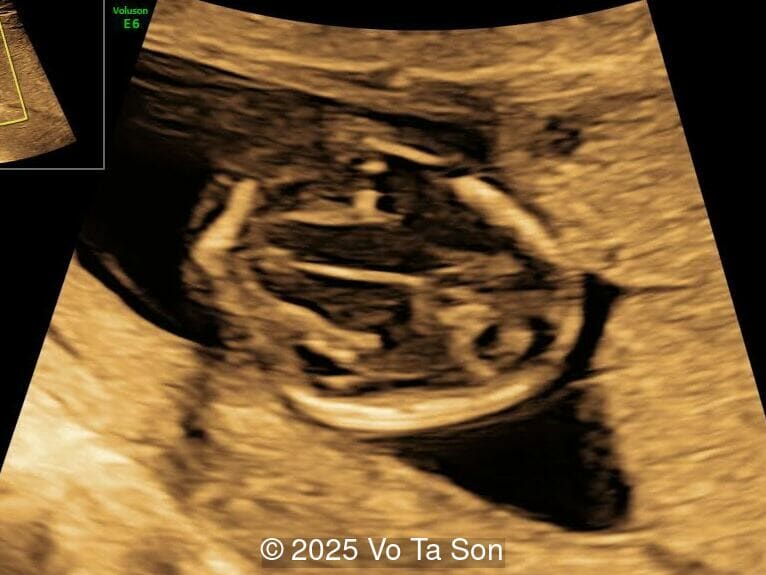

We present a case of Triploidy with a 69,XXY chromosomal complement and open spina bifida in the first trimester.

• Open spina bifida in the sacral region with dry brain sign, crash sign, BS/BSOB >1, and a lesion at the sacral coccygeal spine. The spinal lesion observed in the sacral region is characterized by a posterior vertebral arch defect and a protruding meningeal sac.

If a triploid fetus survives to the second trimester, structural anomalies can be detected by ultrasound and occur in approximately 44-49% of fetuses [4,11]. These include anomalies of the extremities (syndactyly of the third and fourth fingers, clubfeet), central nervous system (holoprosencephaly, Dandy-Walker malformation, agenesis of the corpus callosum, neural tube defects), face (micrognathia, microphthalmia), as well as omphalocele, cardiac anomalies, and renal anomalies [6,7]. The most common findings are syndacyly, occurring in approximately 70% of cases [11], and central nervous system anomalies, which are found in approximately 40% of cases [11], with myelomeningocele found in 9-13% of fetuses with triploidy [8,11-12]. Cardiac defects occur in 13%, of which 9% are ventricular septal defect [11]. If these defects are seen in a growth-restricted fetus, triploidy should be considered in the differential diagnosis and amniocentesis offered, especially if the placenta is enlarged and contains cysts. Features of a partial hydatidiform mole occurs in 24-33% of cases with triploidy [4,11]. Additionally, theca lutein cysts may develop in the maternal ovaries due to high levels of human chorionic gonadotropin [6,7].